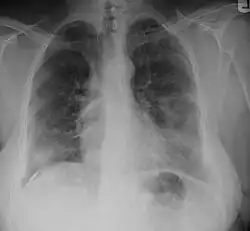

A "B" reader is a physician certified by the National Institute for Occupational Safety and Health (NIOSH) as demonstrating proficiency in classifying radiographs of the pneumoconioses.